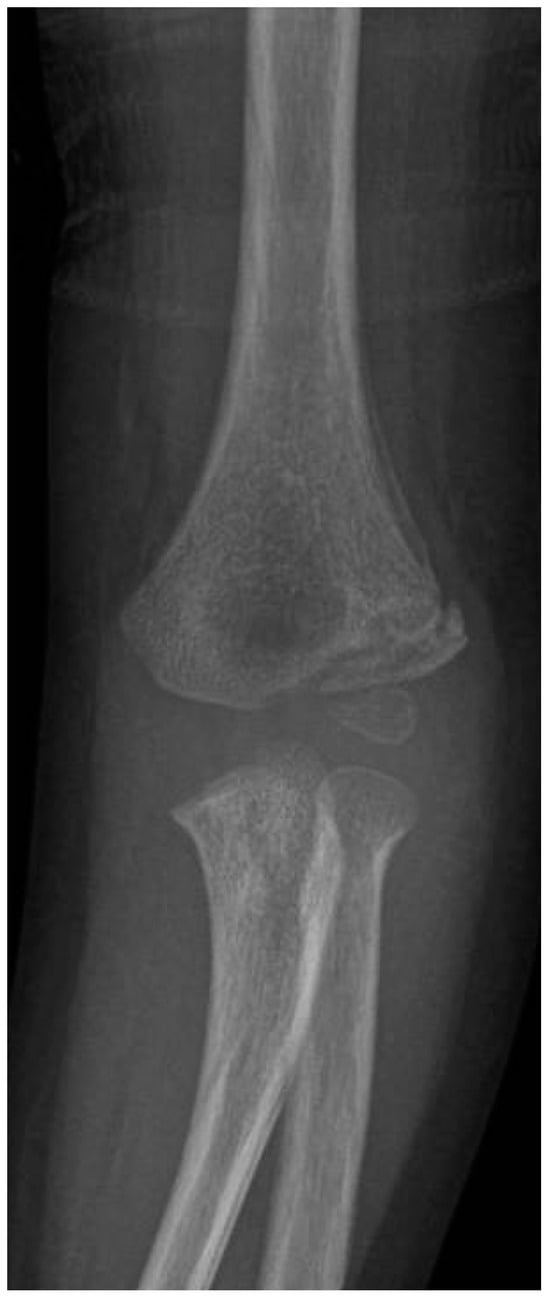

Lateral Humeral Condyle Fracture in Childhood: Results of a New Surgical Technique